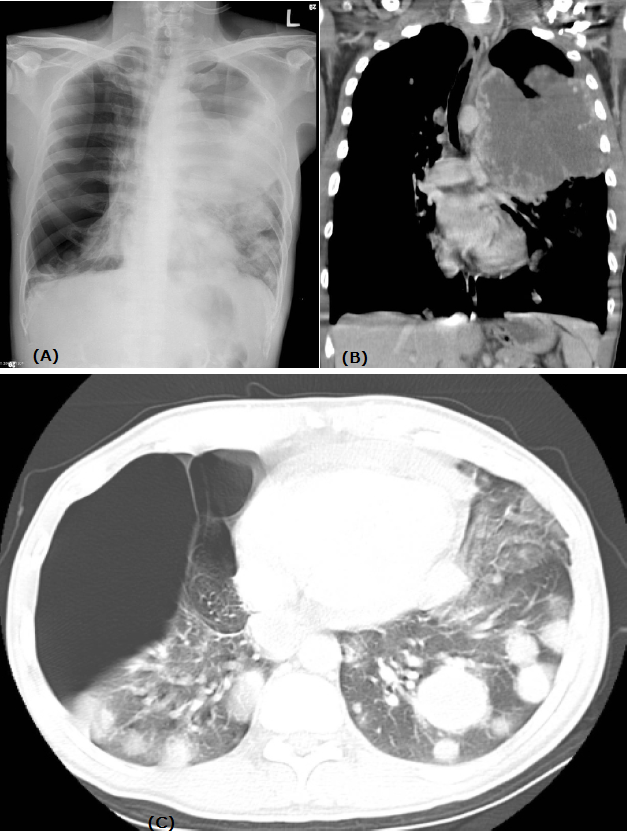

Figure 1: (A) Chest radiograph shows opacity of left lung and a hyperlucent right lung. There are multiple nodules in both lungs.

(B) Contrast-enhanced computed tomography (CT) reformatted image shows a bulky, ill-circumscribed mass with central necrosis arising from anterior mediastinum.

(C) Axial lung window setting shows multiple round nodules in bilateral lungs and large bullae in the right lung.